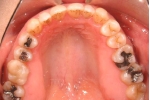

| 初診時

| マルチブラケット終了時